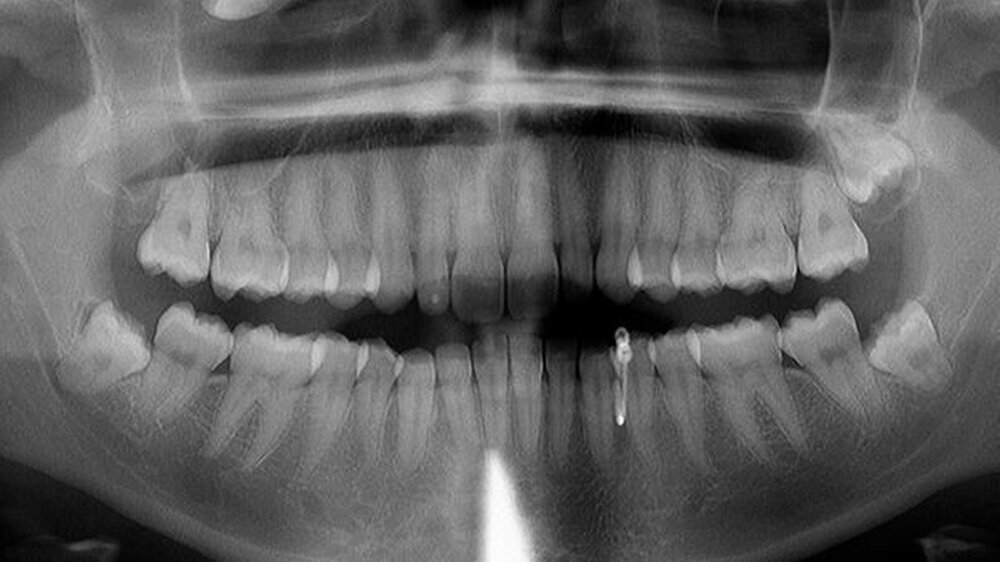

Röntgen (OPG Abb.1): verschattete Kieferhöhle rechts mit extrem verlagertem Zahn 18 direkt infraorbital

Differenzialdiagnostisch stand so der Verdacht auf eine atypische Neuralgie im Bereich des Nervus infraorbitalis rechts (im Sinne einer Trigeminusneuralgie) im Raum. Anamnestisch – die junge Frau war seit ihrem vierten Lebensjahr in unserer Praxis Patientin – war schon eine Dentitio tarda diagnostiziert. Da aber im Bereich des I. Quadranten bereits ein verlagerter Weisheitszahn 18 bekannt war, wurden zunächst folgende weitere Befunde erhoben: